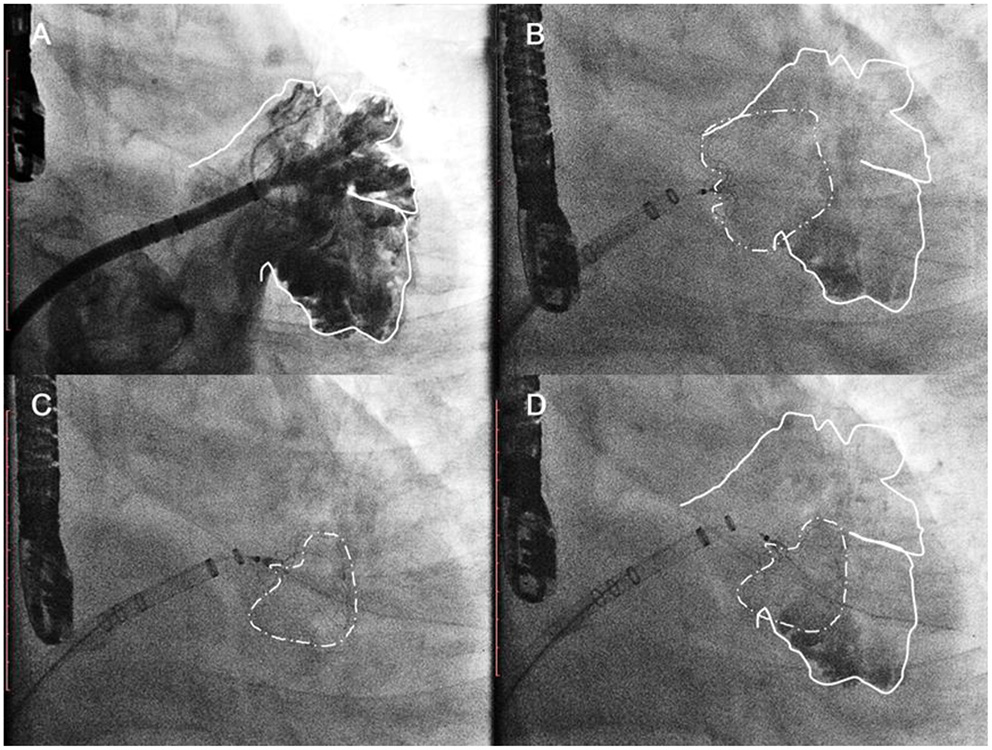

The procedures were performed via femoral access and were guided by both TEE and angiography. A mid-transseptal puncture and a posterior transseptal puncture were performed. After the transseptal puncture, heparin was given to keep ACT above 250 s. Once selective angiograms were performed (Figure 2, Step 1), TEE and angiographic measurements were used to choose the size of the device. A 33-mm Watchman device was initially chosen for every case. However, if the LAA could not be completely sealed with a shoulder hanging outside the LAA (Figure 2, Step 2), the one-stop implantation of double Watchman was chosen for these patients. In the first-implantation step, we chose an appropriately sized device to close the more challenging lobe of the LAA (Figure 2, Step 3). The tug test and TEE were used to evaluate the Position, Anchor, Size, and Seal (PASS) criteria with the first device (Figure 2, Step 4).

Figure 2

The common implantation strategy sequence. Step 1 (A) initial angiographic injection at right anterior oblique (RAO) 30°Caudal 20; Step 2 (B) a 33-mm Watchman device was initially chosen as the first attempt. Acquiring detail of the LAA anatomy through the TEE/CTA images was necessary before the dual-device strategy was selected. Step 3 (C) In the first implantation step, we chose an appropriately sized device to close the more challenging lobe of the LAA. Step 3 (D) The tug test and TEE were used to evaluate the PASS criteria with the first device.

Double-Sheath Strategy

In the first case, the second transseptal puncture was performed via the same femoral site (Figure 3, Step 5); the pigtail catheter with the second access sheath was delivered carefully to the uncovered lobe parallel to the first access sheath, and selective angiography was performed (Figure 3, Step 6). The second Watchman device was chosen according to the uncovered lobe and was carefully placed next to the first device (Figure 3, Step 7). The tug-test was performed on the two devices by pulling the parallel delivery system simultaneously (Figure 3, Step 8). The two devices were released after the PASS criteria had been met with both devices (Figure 3, Step 9).

Figure 3

Double-sheath strategy. Step 5 (A) the second transseptal puncture via the same femoral site; Step 6 (B) the selective angiography of the second lobe was made; Step 7 (C) the second Watchman device was chosen according to the uncovered lobe; Step 8 (D) the tug test was performed on the two devices simultaneously; Step 9 (E) the two devices were released after the PASS criteria had been met with both devices.